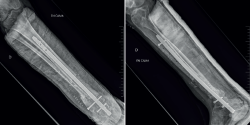

Se realiza en 2 tiempos mediante la técnica de las membranas inducidas de Masquelet. En un primer tiempo se necesita una resección agresiva de los tejidos infectados y toma de muestras intraoperatorias, con posterior inclusión de un espaciador de cemento y estabilización(4). En este caso, resección ósea ampliada de 10 cm incluyendo la articulación del tobillo, toma de muestras, espaciador de cemento con vancomicina y estabilización interna con un clavo de Steinmann (Figuras 6 y 7). Los cultivos intraoperatorios son positivos para para Staphylococcus epidermidis sensible a la meticilina (SEMS). Se ajusta la pauta antibiótica suspendiendo la ceftazidima y continuando con la vancomicina. Los fragmentos de hueso enviados a anatomía patológica son informados como fibrosis parcheada en espacios medulares con focos inflamatorios crónicos y discreta proliferación vascular. Se confirma el diagnóstico. El paciente se va de alta hospitalaria con trimetoprima/sulfametoxazol 160 mg/800 mg 1 comprimido/12 h por vía oral (v.o.) durante 6 semanas.

Figura 6. Control radiológico postoperatorio tras el primer tiempo quirúrgico de resección ósea de 10,7 cm incluyendo la articulación del tobillo, inclusión del espaciador de cemento y estabilización con clavo de Steinmann.